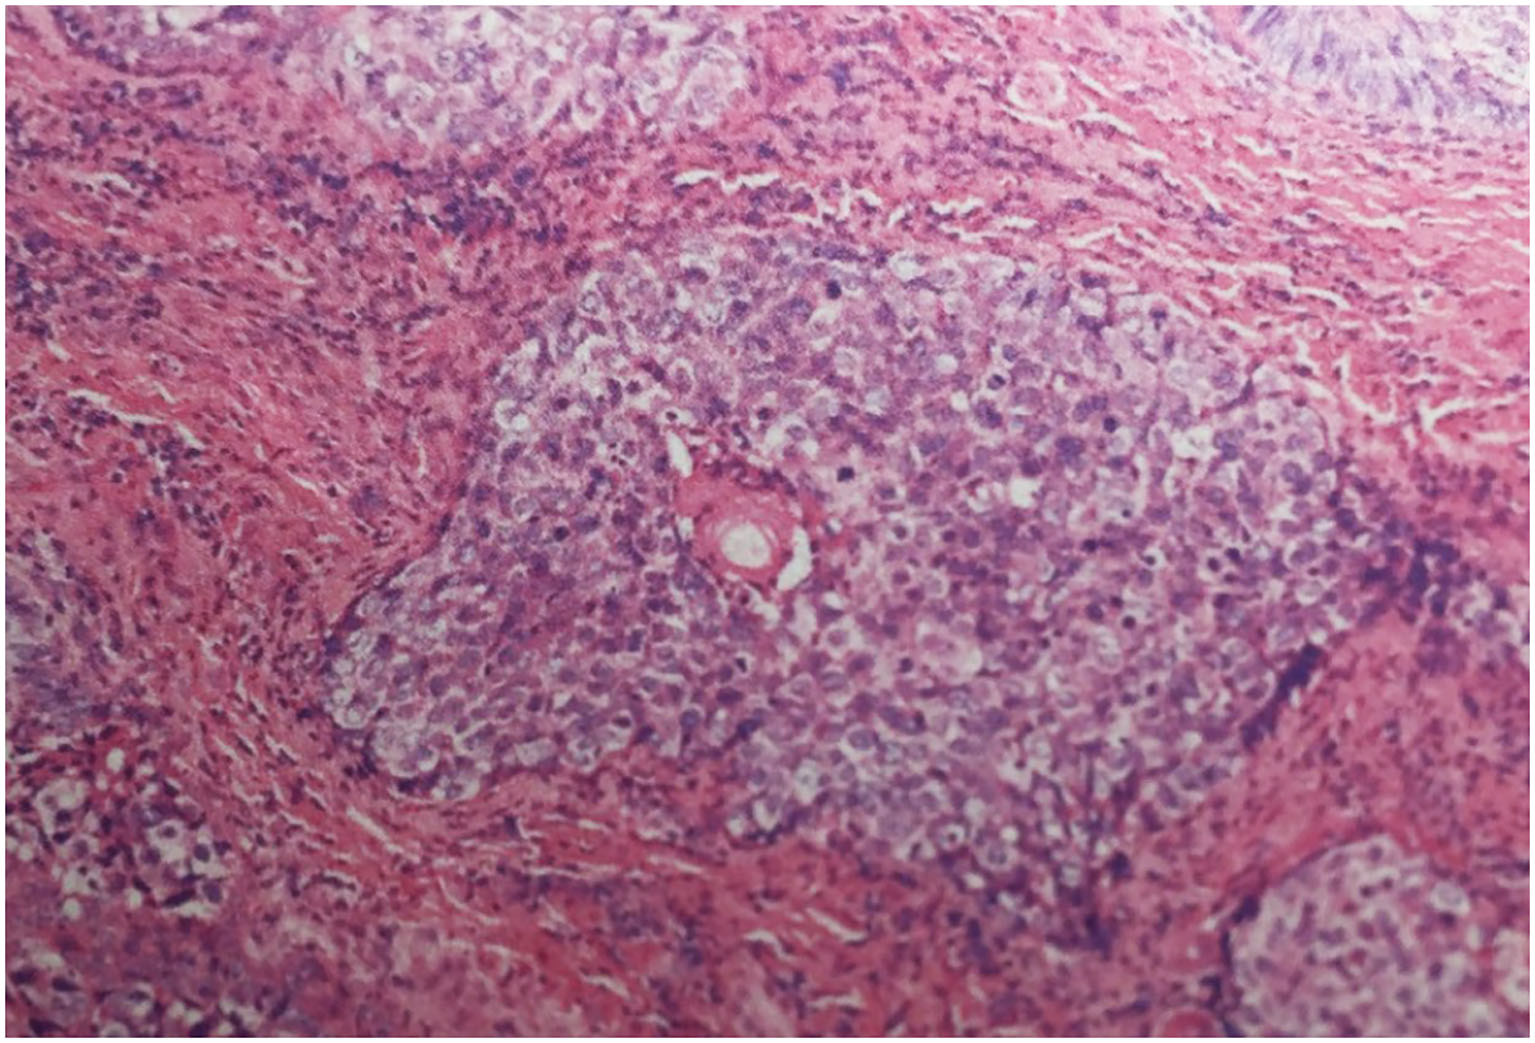

Figure 2

Histological section demonstrating infiltrative lobules of clear cells composed of large, polygonal, clear cells with eccentric nuclei (Haematoxylin-eosin stain; magnification Ć200).

A 68-year-old female presented with 2 months history of redness, pain and blurred vision in the left eye. The slit-lamp examination revealed slight keratinization and multiple abnormal lashes on the left upper eyelid, clogged meibomian glands, and congestion and edema of the conjunctiva. Furthermore, diffused corneal epithelial punctate defect and neovascularization, especially a 4 à 3 mm sized irregular corneal epithelial defect was observed at the temporal cornea. The most crucial observation was the presence of 1 à 2 mm sized aseptic corneal perforation existed in the central cornea, causing iris incarceration (Figure 1A). The patients did not have a history of eye surgery or ocular trauma, or the immune-related disorders of rheumatoid arthritis, sjögren's syndrome, and infectious keratitis typically associated with corneal perforation. Routine investigations were also performed to rule out mite infestation, bacterial or viral infection, allergic blepharositis and seborrheic blepharositis. Accordingly, we predicted that the rough eyelid margin resulting from severe MGD might be responsible for persistent corneal epithelial defect, neovascularization, perforation, and blepharitis. In order to prevent ulcer enlargement and intraocular infection, penetrating keratoplasty with a 7.5 mm graft size was performed immediately. During 2 months follow-up period, the graft remained clear and no serious complications occurred. However, several small nodules gradually developed on the rough eyelid margin which accompanied with bleeding, burst and madarosis (Figure 1B). Subsquently, to probe the reason of persistent rough eyelid we performed biopsy. Suprisingly, we observed a tumor attached to epidermis which infiltrated the hair follicle within the dermis. We diagnosed the tumor as TLC, as the sections demonstrated classical large, polygonal, clear cells with eccentric nuclei and trichilemmal keratinization (Figure 2). TLC was immediately managed by lesionectomy. Postsurgery, the patient underwent the routine treatment for the ocular surface and was transferred to the oncology department for further general examination, which revealed no metastasis, so that chemoradiothreapy was not performed. During 1 year follow-up period, there was no evidence of local recurrence and metastasis, and the corneal graft was transparent (Figures 1C,D).